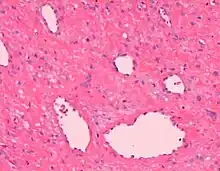

Angiofibroma, Hematoxylin and eosin stain, magnification ×10.

AGF lesions share common macroscopic (i.e. gross) and microscopic appearances. Grossly, AGF lesions consist of multiple papules, one or more skin-colored to erythematous, dome-shaped nodules, or usually just a single tumor. Microscopically, they consist of spindle-shaped and stellate-shaped cells centered around dilated and thin-walled blood vessels in a background of coarse bundles of collagen (i.e. the main fibrous component of connective tissue).[2] Angiofibromas have been divided into different types but commonly a specific type was given multiple and very different names in different studies.[2]